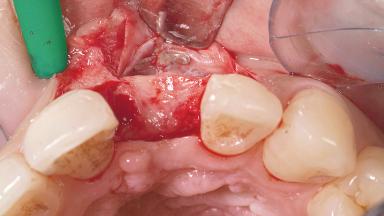

A 30-year-old female patient had lost tooth 21 and was referred to our clinic for consultation and treatment. Due to advanced apical infection, tooth 21 had been extracted two months earlier at another clinic and an acrylic-resin tooth had been bonded to the adjacent teeth. The patient desired implant treatment to avoid any damage to the adjacent natural teeth. While the patient had no history of any systemic disorder, she was a heavy smoker and exhibited medium to advanced periodontitis in the entire jaw. After the initial treatment to achieve a pocket probing depth of less than 4 mm and no bleeding on probing, a decrease in the height of the papillae mesial and distal to the extraction site and overall gingival recession were observed.

| Bone Augmentation | Horizontal|Staged |

| Augmentation Materials | Autogenous chips|Membrane |

| Bone Volume | Deficient horizontally, requiring prior grafting |